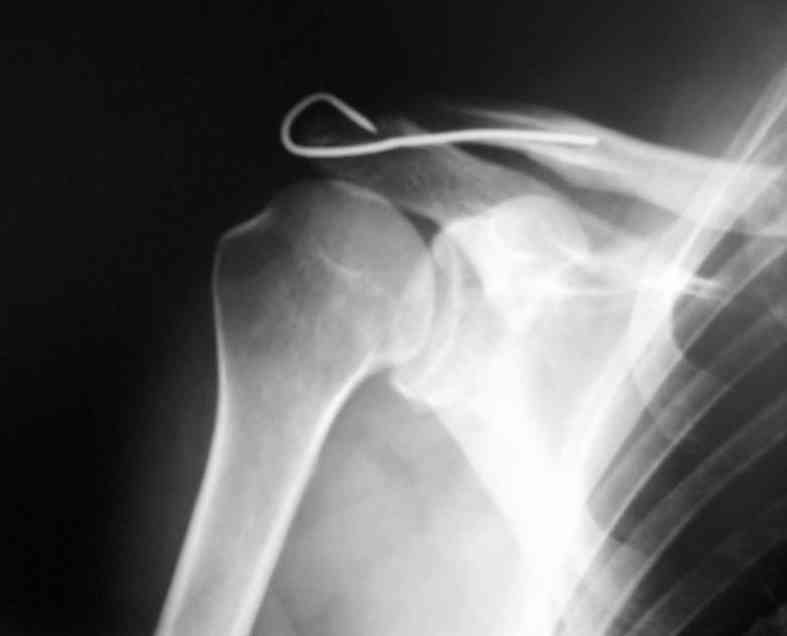

Уважаемые коллеги,высылаю протокол операции (если кому пригодится, буду рад)

Внешний вид больного (травма: 09.10.2007, операция: 11.10.2007) Ориентиры доступа: овальный – пальпируемый акромиальный конец ключицы, линейный – операционный разрез

Отпрепарированы м\ткани по передней поверхности акромиона Выведен в рану акромиальный конец ключицы

Иссечение разорванного мениска

Подготовка канала в акромиальном конце ключицы сверлом 2,8 мм

Введение крючка в подготовленный канал Дистальная часть крючка подведена под акромион и фиксирована на нем путем загибания (вывих ключицы устранен)

Изготовление крючка из стержня.

Здравствуйте.Извиняюсь за задержку. Фотографии фиксации АКС. Канал для ножки фиксатора формируется затупленным шилом, для уменьшения опасности перфорации кортикального слоя.

В некоторых клиниках активно применяли конструкции из никелида титана (с термомеханической памятью) с фиксацией за ключицу и клювовидный отросток. Сам не применял, но отзывы были хорошие а рентгенограммы красивые.